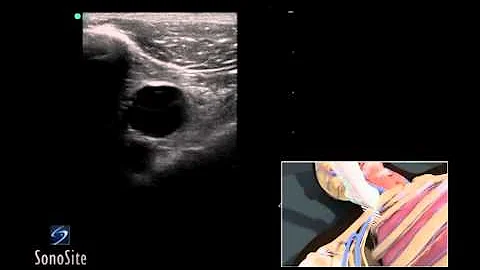

How To: Ultrasound Guided Insertion Internal Jugular Catheter (long) 3d Video

Visit http://www.sonosite.com/education for more videos like this one. Using 3D animations we have come up with a new way of ...